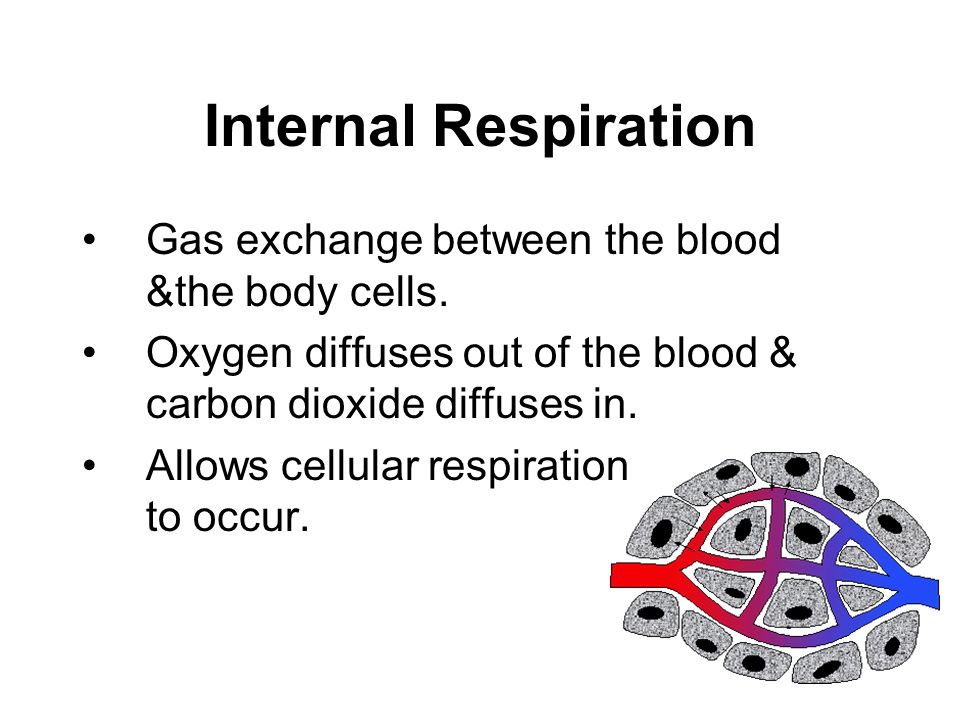

2. Internal Respiration:

This involves the breaking down of food substances and release of energy. It takes place within the cells of the body.

2. Internal Respiration:

This involves the breaking down of food substances and release of energy. It takes place within the cells of the body.